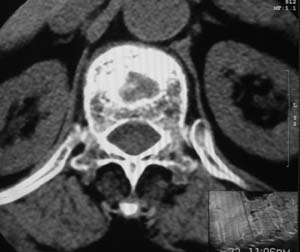

患者,女,72岁,胸背部疼痛3月余,无明显外伤史。曾应用局部封闭、非甾体类止痛药治疗效果不明显,近来疼痛缓解频感背困,平卧缓解,近日行ct检查发现胸12椎体病变,烦请同道发表意见,诊断什么?有何治疗经验!谢谢!!!

标绘图示:第十二胸椎级第一腰椎椎体楔形改变。ct扫描示:第十二胸椎椎体骨质结构紊乱,并可见一囊状低密度影,边缘可见硬化,椎体皮质完整。

考虑:第十二胸椎陈旧性骨折、许莫氏结节。